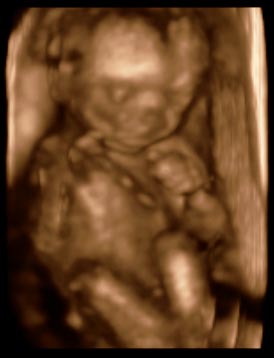

Tegnap voltunk 4d Uh-on. Minden a legnagyobb rendben. Nagyon szépen fejlődnek és méretük tökéletesen megfelel egy baba méretének. Szervek is rendben vannak. :D Bogi türelmesen végig üldögélte törökülésben az uh-ot és nagyon szégyelős volt :D Boti viszont ide-oda mozgott, állandóan menekült az uh elől :D Már szinte sajnáltam :?

Ő Bogikám:

Kép

Ő pedig Botikám:

Szilvi

Szilvaqueen,

Jók a képek! :wink: Hol voltatok 4D-n?

Mi is tegnap voltunk 4D-s uh-n. Hát nagyon-nagy élmény volt.

Tüzetesen átnézte az uh-s hölgy mindkét punást, és azt mondta minden rendben van. Azt mondja donga lábra utaló jel nincsen, ha lenne, akkor azt egyből ki lehetne szúrni, mert az annyira tipikus. Ha meg néha befelé is fordítják, az nem baj, mert ilyenkor a babák nagy része így csinálja!

Jaj, annyira aranyosak voltak, összedugták a fejüket, meg a lábukat is! :lol: Szokás szerint mint két sajtkukac úgy járt mindenük sokszor! Nőttek is egész szépen a másfél héttel ezelőtti uh-hoz képest, egy pár nappal nagyobbnak is mérte őket.